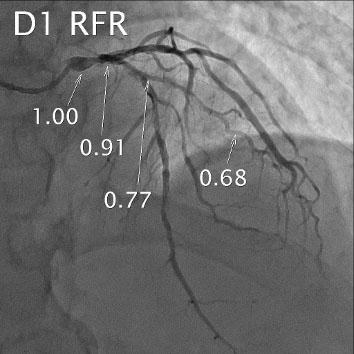

LAD FFR & Dx RFR